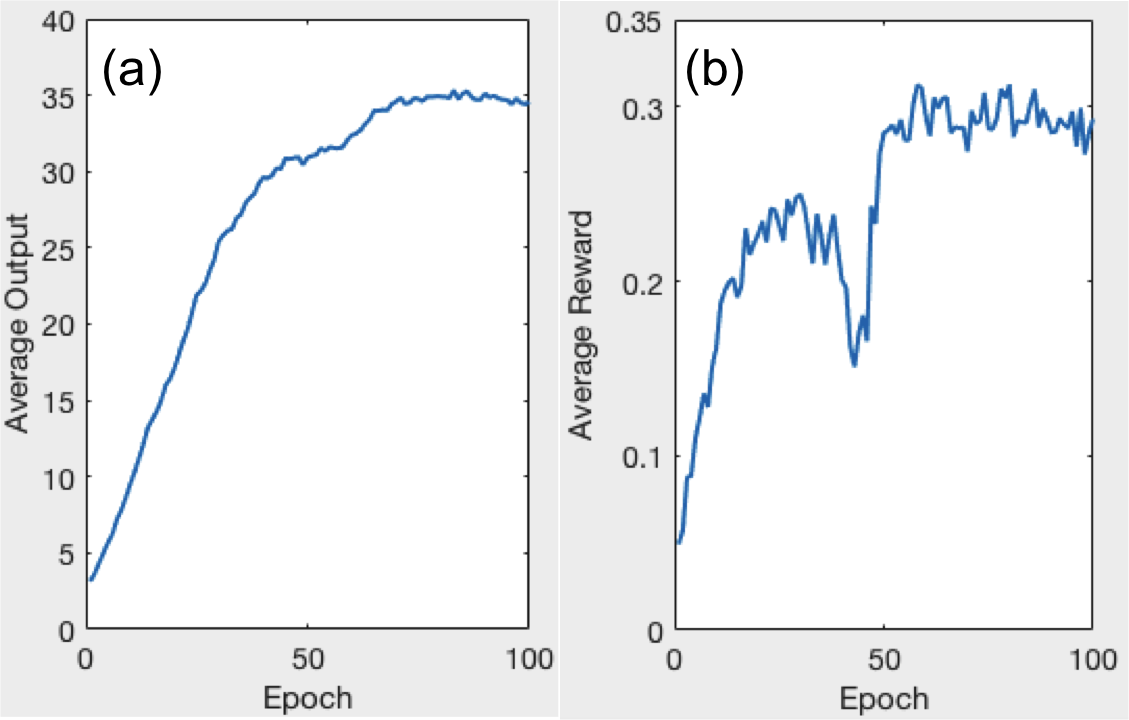

During the training process, we monitor the quality of the trained PTPN shown in Fig. 4. Both the average output of the PTPN and the reward follow an increasing trend although with some oscillations. This indicates that the PTPN is adjusted gradually in this reinforcement learning process towards predicting actions with high reward values.